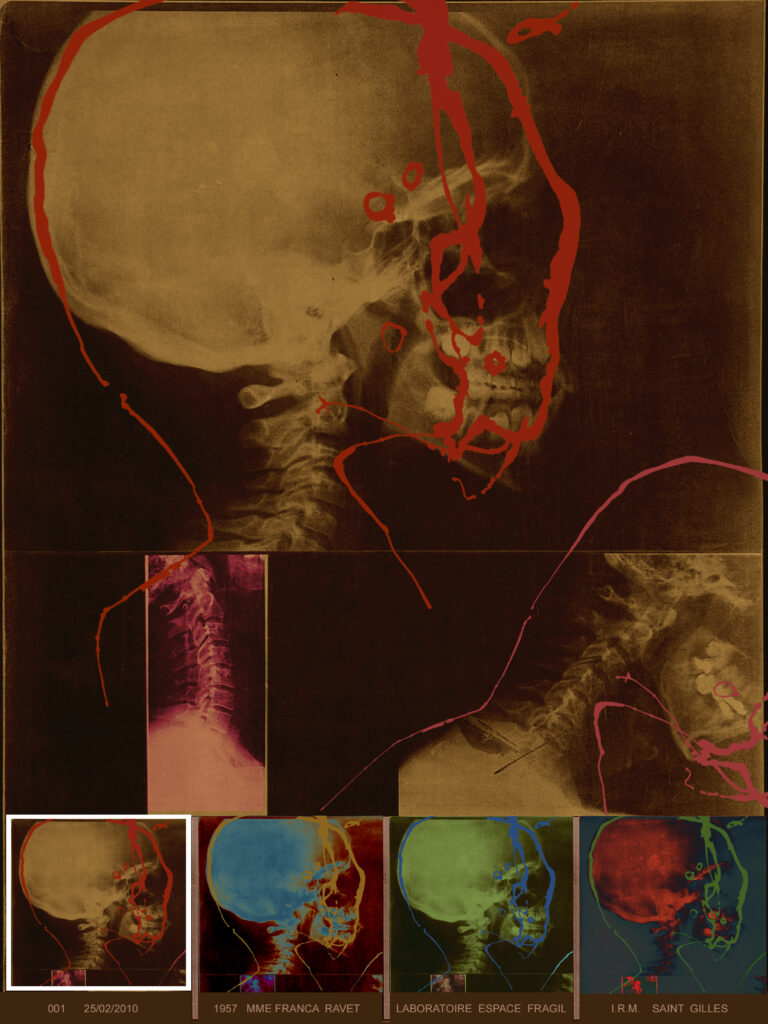

L’artiste est partie d’une empreinte graphique donnée qu’elle assimile à “une sorte d’IRM cérébral”, répétée de manière obsessionnelle et répétitive.

Du point de vue du sens, Ravet restitue ce processus de “conception, de transmission et d’effacement des informations mémorisées tout au long de nos vies”.

En livrant également des grands formats “diasec” sur plexiglas, elle impose un traitement numérique à sa peinture. C’est alors forcément toute la question du fichage et du stockage des données informatiques qui apparaît.